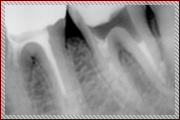

上記は歯のレントゲン写真です。二本足のように、歯が歯茎に埋まってますが、右の歯の黒い部分(二本足のつけ根の部分)が菌に冒されてます。 |

非常に細かい部分ですが、顕微鏡を使い、菌に犯されているところを治療した後にレントゲンを取りました。 |